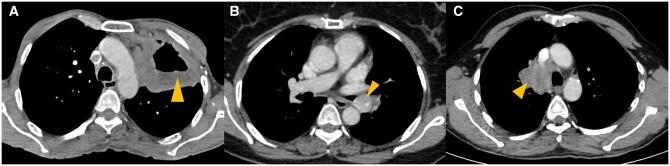

Lung cancer is the second most commonly diagnosed cancer worldwide. In the present era of targeted therapy for various lung cancer mutations, it is essential to be aware of the imaging correlates of various lung cancer mutations on contrast enhanced computed tomography of thorax. In this article, we have discussed the imaging patterns of various types of lung cancer including different mutations and also comprehensively reviewed the imaging recommendations (National Comprehensive Cancer Network [NCCN], European Society of Medical Oncology [ESMO] and American Society of Clinical Oncology [ASCO]) and management guidelines of lung cancer (non-small cell, small cell and other neuroendocrine tumours). We have also discussed guidelines for screening, diagnosis, staging (recent 9th edition tumour node metastasis [TNM]), treatment response evaluation, and follow up. Role of interventional radiology in the treatment of primary lung cancer, lung metastasis, and management of posttreatment complications, have also been described in detail in this article. In addition, current status of artificial intelligence in lung cancer has also been briefly discussed.

肺癌是全球第二大常见的确诊癌症。在当前针对各种肺癌突变进行靶向治疗的时代,了解胸部对比增强计算机断层扫描上各种肺癌突变的影像学关联至关重要。在本文中,我们讨论了包括不同突变在内的各种类型肺癌的影像学模式,并全面回顾了肺癌(非小细胞、小细胞和其他神经内分泌肿瘤)的影像学建议(美国国立综合癌症网络 [NCCN]、欧洲医学肿瘤学会 [ESMO] 和美国临床肿瘤学会 [ASCO])及管理指南。我们还讨论了筛查、诊断、分期(最新第9版肿瘤淋巴结转移 [TNM])、治疗反应评估和随访的指南。本文还详细描述了介入放射学在原发性肺癌治疗、肺转移以及治疗后并发症管理中的作用。此外,还简要讨论了人工智能在肺癌方面的现状。